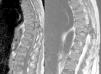

In January 2014, she was hospitalised for thoracolumbar pain and lower limb paresis. MRI findings were consistent with a 3.7cm brown tumour in vertebral posterior elements in D10 and a smaller tumour in L2. She also had widespread bone disease with chronic fractures and “rugger jersey” sclerosis (Figs. 1 and 2). Persistent severe hyperparathyroidism was observed in lab tests, and so a new imaging study (ECHO and parathyroid scintigraphy) was requested which confirmed the existence of a fifth retrotracheal left paratiroidea gland (Fig. 3).

Thoracolumbar MRI: sagittal plane of MRI in T1 and T2 of the thoracolumbar spine showing a focal lesion in the left posterior elements of the D10 vertebra involving the pedicle, pars, and lamina. The lesion has an expansive character and is surrounded by a thin, newly-formed shell of periosteal bone with a maximum diameter of 3.7cm, presenting soft tissue components and invading the spinal canal, resulting in clear cord compression with narrowing. An intermediate signal is observed in all pulse sequences and we believe it is consistent with a brown tumour (osteoclastoma).1,2